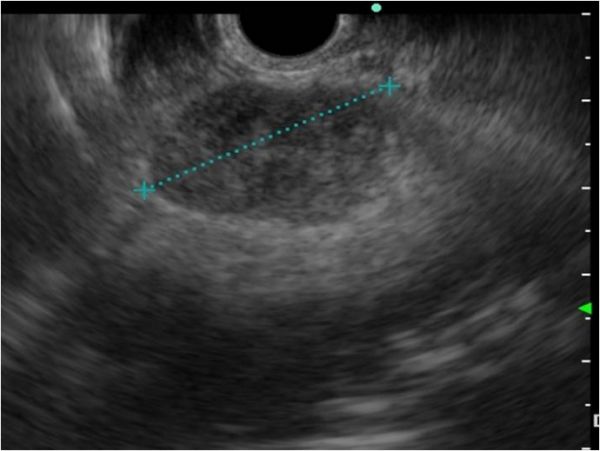

Die obere Endosonographie (EUS=Endo-Ultraschall) ist eine endoskopische Methode, die es erlaubt, den oberen Magendarmtrakt (Speiseröhre, Magen, Zwölffingerdarm, Gallenwege und Bauchspeicheldrüse) zu spiegeln und gleichzeitig mittels Ultraschall zu untersuchen. Sie ist die Methode der Wahl, um Gallengangssteine sicher zu entdecken oder auszuschliessen, die Ursache einer Bauchspeicheldrüsenentzündung (Pankreatitis) zu untersuchen, Bauchspeicheldrüsentumoren zu punktieren oder Speiseröhren- bzw. Magentumoren genau zu charakterisieren, damit die richtige Behandlung durchgeführt werden kann.

Das knapp 1cm dicke Endoskop enthält an der Spitze neben einem Videochip einen kleinen Ultraschallkopf und wird beim schlafenden Patienten durch den Mund in die gewünschte Region (Speiseröhre, Magen oder Zwölffingerdarm) eingeführt. Dabei können auch die jeweils angrenzenden Regionen untersucht werden wie Brustkorb in der Speiseröhrenregion, Bauchhöhle in der Magenregion und Bauchspeicheldrüse in der Region des Zwölffingerdarmes. Bei Bedarf kann auch durch ultraschallgesteuerte, millimetergenaue Punktion mittels Feinnadel aus dem Gewebe Material zur mikroskopischen Untersuchung gewonnen werden.